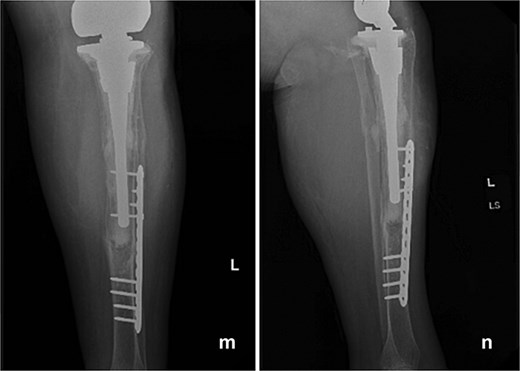

At 6 months postoperatively, the patient sustained a tibial shaft fracture following a pivoting injury while exiting her vehicle. She underwent operative fixation with a plate and was managed initially in a splint, followed by transition to a controlled ankle motion (CAM) boot. At 1 year follow-up from index procedure, she continued to progress well, with intact fixation and a stable total femur construct (Fig. 4). Although this subsequent injury was unrelated to the index procedure but is included for completeness and transparency in her clinical course.

Follow-up anteroposterior (m) and lateral (n) radiographs at 1 year demonstrating intact tibial fixation following fracture repair and a stable total femur construct without evidence of loosening or reinfection.